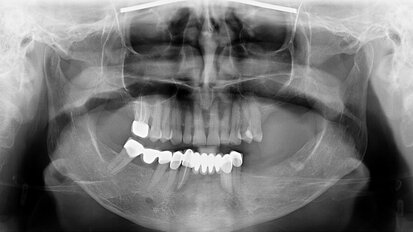

The piece highlights that 85% of facial pain cases are odontogenic, but the remaining 15% are non-odontogenic in origin, requiring specialised care from OFP experts. Non-odontogenic OFP has various aetiologies, including musculoskeletal, neuropathic and neurovascular disorders.